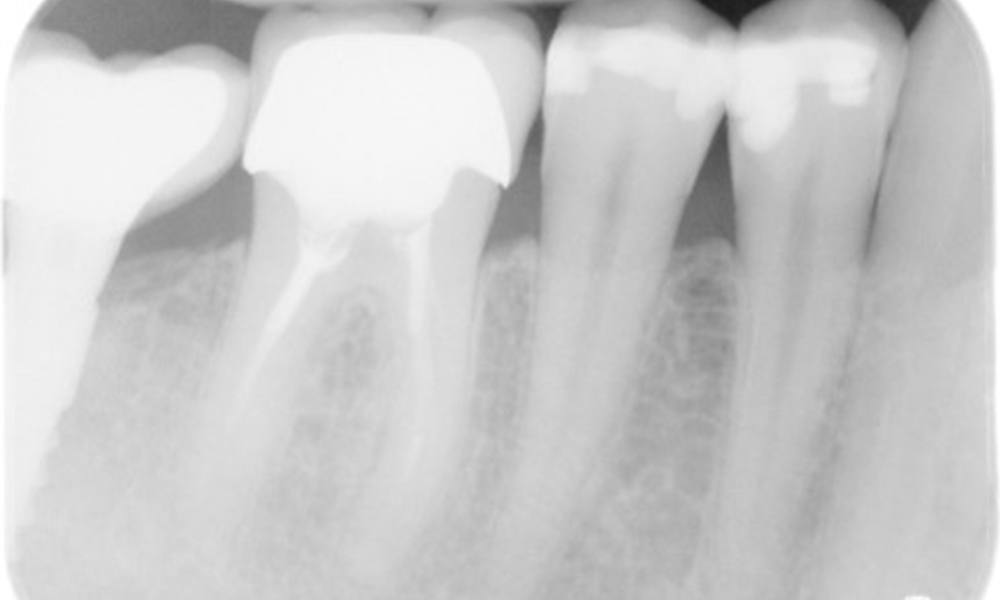

Der Patient hat einige zahnärztliche Restaurationen und zwei Implantate (2. und 4. Quadrant). Anhand der aktuellen Befunde lässt sich eine Gingivitis bei stabilem parodontalen Zustand am reduzierten Parodont (Stadium III, Grad A) feststellen.

Versorgungen: zahnärztliche Restaurationen (NEM keramisch verblendet), zwei Implantate (2., 4. Quadrant)

Der Patient zeigt keine besonderen Risikofaktoren mit spezifischen zahnmedizinischen Auswirkungen. Daher ist der aus der Mundgesundheit ermittelte Bedarf maßgebend. Hierbei zeigt sich eine gute Mundgesundheit mit stabilem, reduzierten Parodont. Sollte sich bei einem Kontrolltermin am Implantat eine Vergrößerung von ST im Vergleich zur Baseline kombiniert mit einer diffusen Blutung zeigen, so sollte eine Röntgendiagnostik (i. S. eines Zahnfilms) erfolgen, um frühzeitig einen periimplantären Knochenverlust zu erkennen und dagegen zu intervenieren.